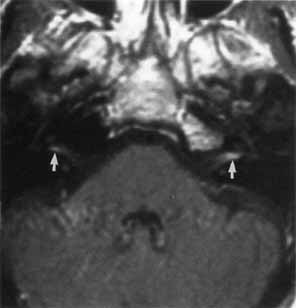

The motor nuclei of the sixth and seventh cranial nerves are initially in close proximity in the pontine subdivision of the metencephalon. As the metencephalon elongates and expands, the facial nucleus migrates ventrolaterally in relation to the abducens nucleus, displacing facial motor axons that loop dorsally in the floor of the fourth ventricle to form the facial colliculus (Fig. 1). This intimate relationship between the abducens and facial motor nuclei is the anatomic substrate for the clinical findings in congenital Möbius' syndrome and in acquired inflammatory, vascular, and neoplastic lesions that involve the intramedullary segment of the facial nerve.

Fig. 1 Cross section of pons, with relationships of facial motor nucleus (VII), abducens nucleus (VI), corticospinal tract, trigeminal nucleus, and tract. Facial colliculus (arrow). (Carpenter M: Core Text of Neuro-Anatomy. 3rd ed. Baltimore: Williams & Wilkins, 1985:152)